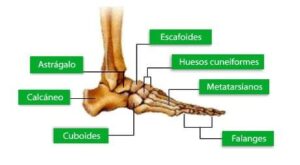

Los huesos cuneiformes (del latín para «cuña») son un conjunto de tres huesos en el lado medial del pie que se articulan con el navicular proximal y con las superficies proximales del metatarsiano 1-3 distalmente.

Al mirar las superficies proximales de los tres huesos vemos una superficie cóncava para que el navicular se resida. El navicular posee tres facetas para la articulación cuneiforme para aumentar conformidad huesuda. La superficie distal crea superficies convexas individuales para los metatarsos 1-3.

El cuneiforme lateral ocupa el centro de la fila delantera de los huesos tarsales, entre el segundo cuneiforme medialmente, el cuboide lateralmente, el navicular detrás, y el tercer metatarsiano en frente.